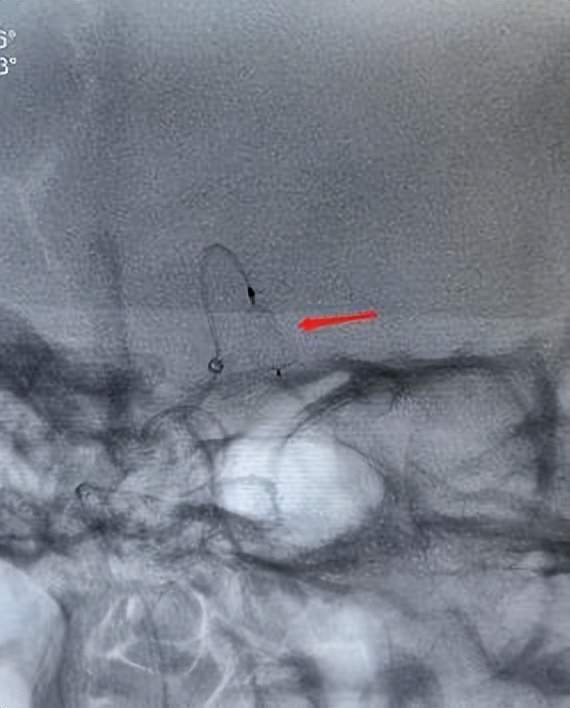

术中图片

经过充分的术前准备,5月10日,神经内科介入团队紧密配合,经过“种子、萌芽、开花”三个阶段,成功为患者实施动脉瘤WEB装置植入手术,为邢阿姨拆除了随时可能危及生命的“炸弹”。术后动脉瘤腔内造影剂即刻滞留,完全达到预期效果。